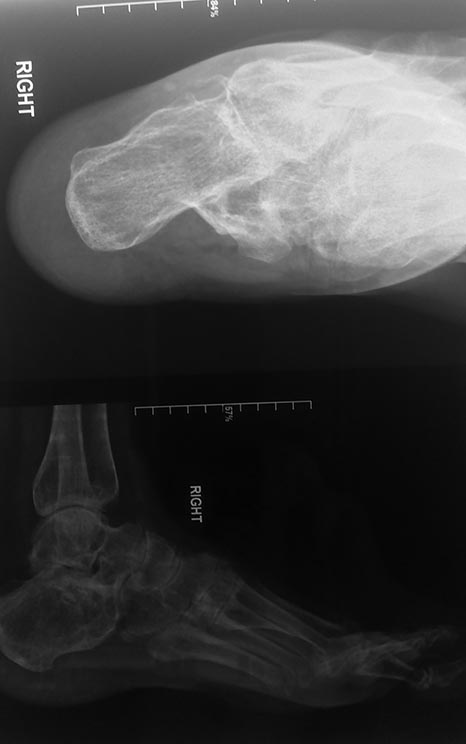

Неправильно сросшийся перелом пяточной и таранной кости

Здравствуйте, уважаемые доктора! Нужен совет - как можно исправить неправильно сросшийся перелом пяточной кости.

После снятия гипса, как смогла наступать на ногу с минимальной нагрузкой, выяснилось, что пятка неправильно срослась, деформирована стопа, заваливалась наружу, нога вставала на ребро, длина стопы уменьшилась на 2 см.

Носила обувь с ортопедическими стельками. Стопа частично выправилась, но деформация все равно осталась достаточно большая, из-за этого я не могу долго ходить, нога быстро устаёт, остаётся хромота, в районе голеностопного сустава остаётся небольшой отек, начались боли в тазобедренном суставе и спине.